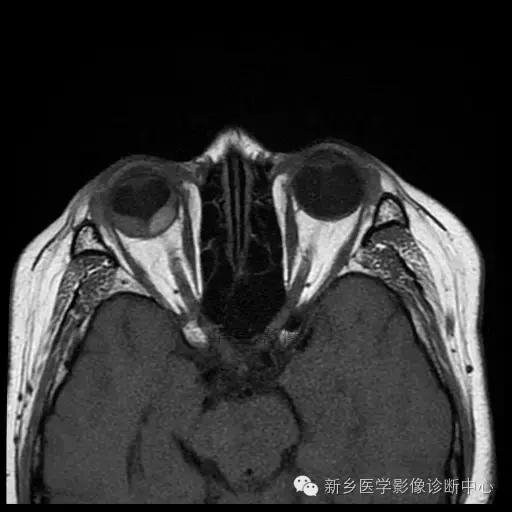

脉络膜黑色素瘤

脉络膜黑色素瘤是由恶性黑色素瘤细胞组成的神经外胚叶性肿瘤, 其组织发生于脉络膜基质内的黑色素细 胞, 国内发病率仅次于发生在儿童的视网膜母细胞瘤, 居眼内肿瘤的第二位, 少数病例可向眼眶蔓延, 晚期向肝脏转移,老年人居多。

影像:

(1)CT:早期眼环局限性增厚;突入玻璃体腔后, 表现 为 密度均匀、边界较清楚的等密度或略高密度半球形或球形肿块;肿瘤较大时,外形不规则, 可占据整个玻璃体腔。可侵犯巩膜外、视神经,可继发视网膜脱离。

(2)MRI:肿瘤边界光 整, 多呈蘑菇型,T1WI呈高或极高信号,T2WI呈低信号。增强扫描肿瘤强化而视网膜及脉络膜下积液及眶内脂肪不强化。